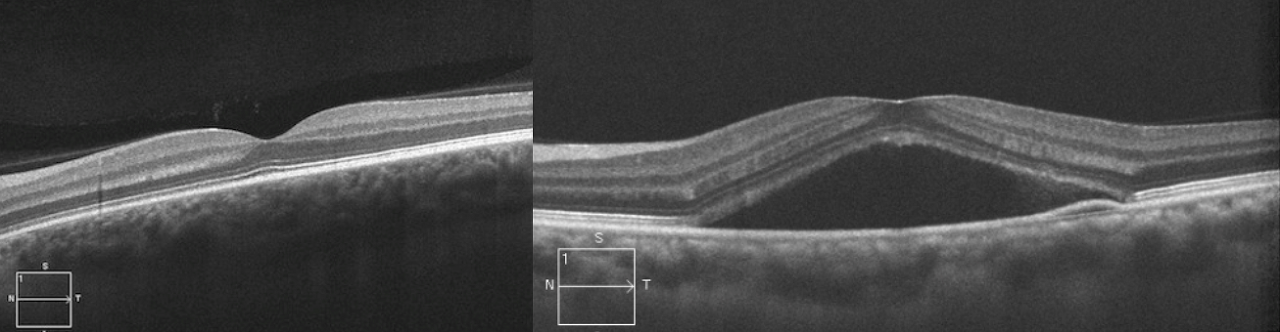

중심장액맥락망막병증은 망막의 중심부에 국한된, 경계가 분명한 장액성 감각신경망막박리 또는 망막색소상피박리가 나타나는 질환입니다. 남자가 여자보다 3~8배 정도 많고 대개 30~50대까지의 건강한 청장년층에서 많이 발생합니다. 주로 중심시력을 담당하는 황반에서 발생하므로 대부분 시력감퇴, 중심암점, 변시증, 소시증, 색각이상 등의 증상을 호소하게 됩니다.